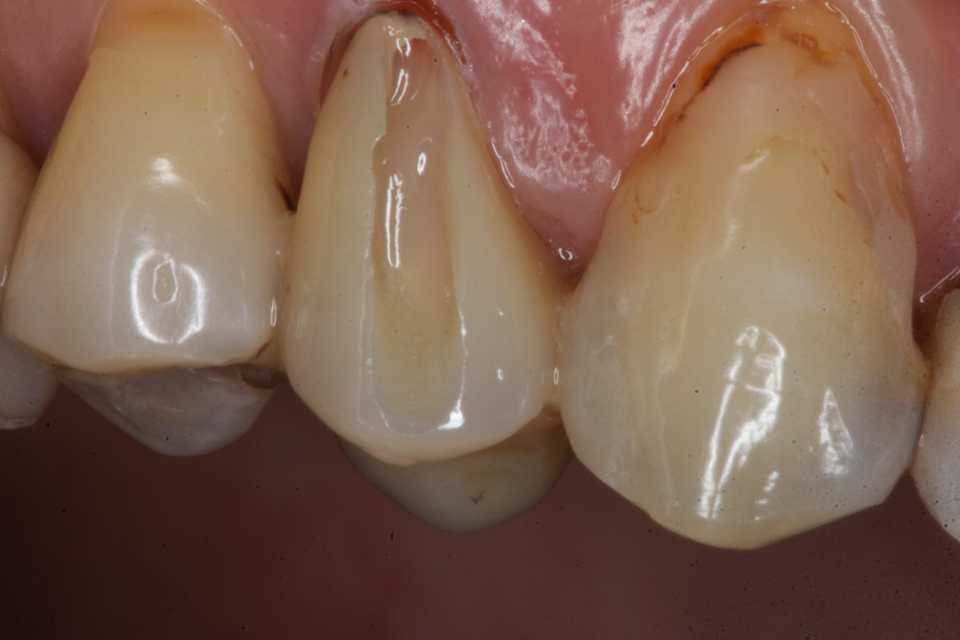

40代女性、右上4、Per+GAPerというのは根管治療後に根管内に感染を起こしている状態でGAとは炎症が根管の外に波及している状態。この方は10年程前に神経を取って被せたということでしたが、2、3年前GAができて別の歯医者に行ったら切って膿を出してもらったら治ったということでしたが、根管に細菌が感染している以上細菌が消えたりしないので、何度も再発します。今回は切開というよりは根管内部に3MIX+α-TCPを入れて根管内部を消毒殺菌しようというコンセプト。内部のポストも根管充填材も完全に除去する必要はない。根管充填材が見えるところまで穴を開けて薬剤を入れ、CRで蓋をするだけでよい。信じられないだろうが、これだけで治る。もし再発するようなら、冠のどこかに隙間があり、そこから細菌が出たり入ったりしているわけだから、冠もポストも除去して隙間を塞ぐ必要がある。多分従来の根幹治療しか知らない歯科医師は何が起こっているのか分からないと思うが、根管治療の真実が分かれば理解できないことはないと思う。一般に思われてる根管治療というのは理想からは程遠いものだということだ。冠にもポストにも根管充填材にも隙間だらけで細菌がその隙間から出入りしているのが現実だ。

僕が使っているボンディング材は​ こちら ​。α-TCPの50%クエン酸練り(硬化する)。

この上からCRダイレクトボンディングでカバーする。​ 3MIX+α-TCP

では時系列でどうぞ